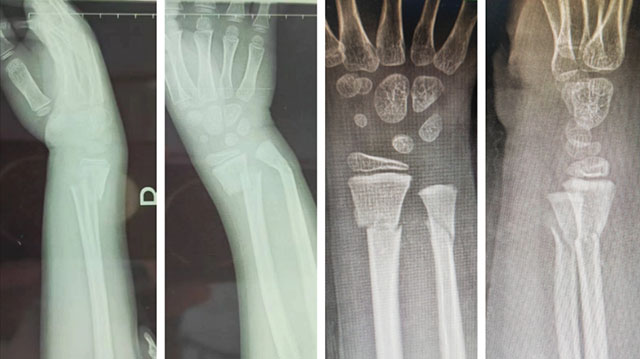

2024年10月2日,泸州又一“爬树哥”从树上跌落,随即右前臂着力,感到疼痛、肿胀、畸形、活动受限,在当地医院诊断为右尺桡骨骨折,转至西南医科大学附属中医医院骨伤科创伤·正骨组进行中医正骨手法复位。

左:复位前 右:复位后

付至江主治中医师接诊后,采用擒拿扶正、拔伸牵引、提按端挤等手法,仅仅几分钟迅速完成骨折复位,患者的疼痛感明显减轻,再敷上骨伤科特制的金黄散,用特制的杉树皮小夹板和独特的包扎技术进行固定。三周后,患者复查骨折已完全复位,拆除夹板,可以活动了。